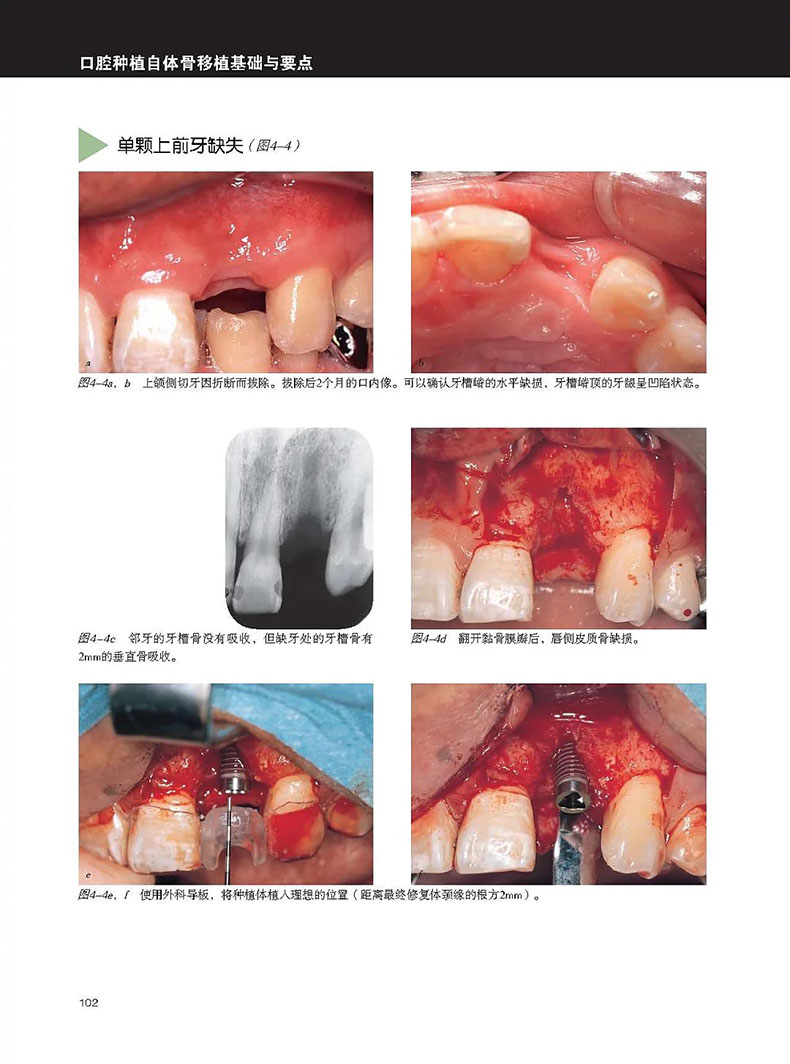

單顆上前牙缺失